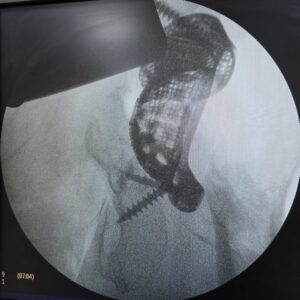

Postoperative Outcome: Stable Fixation After Complex Hip Revision

The implant was successfully placed in the appropriate position.

Postoperative imaging confirmed coverage of the defect and implant fixation.